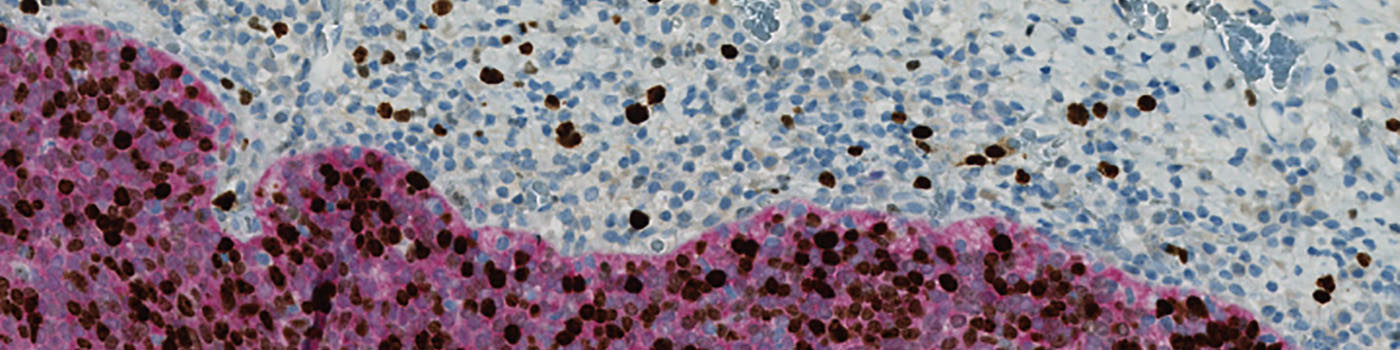

Figure 1

One field of view of the original image at 20X.

Figure 2

Segmentation of brown positive (green label) and blue negative (blue label) nuclei in the image. All nuclei detected are surrounded by cytoplasm. A white labeled cytoplasm is considered tumor tissue and cytoplasm with turquoise labeling is considered non cancerous tissue.

Figure 3

Detection of nuclei surrounded by p16 (red) cytoplasmic staining. Positive double stained nuclei are labeled green and negative double stained nuclei are labeled blue.